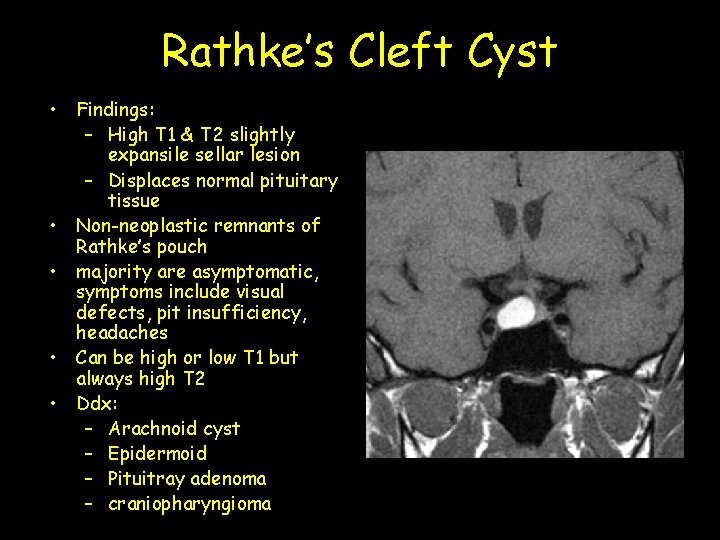

Rathke’s Cleft Cyst • Findings: – High T 1 & T 2 slightly expansile sellar lesion – Displaces normal pituitary tissue • Non-neoplastic remnants of Rathke’s pouch • majority are asymptomatic, symptoms include visual defects, pit insufficiency, headaches • Can be high or low T 1 but always high T 2 • Ddx: – Arachnoid cyst – Epidermoid – Pituitray adenoma – craniopharyngioma